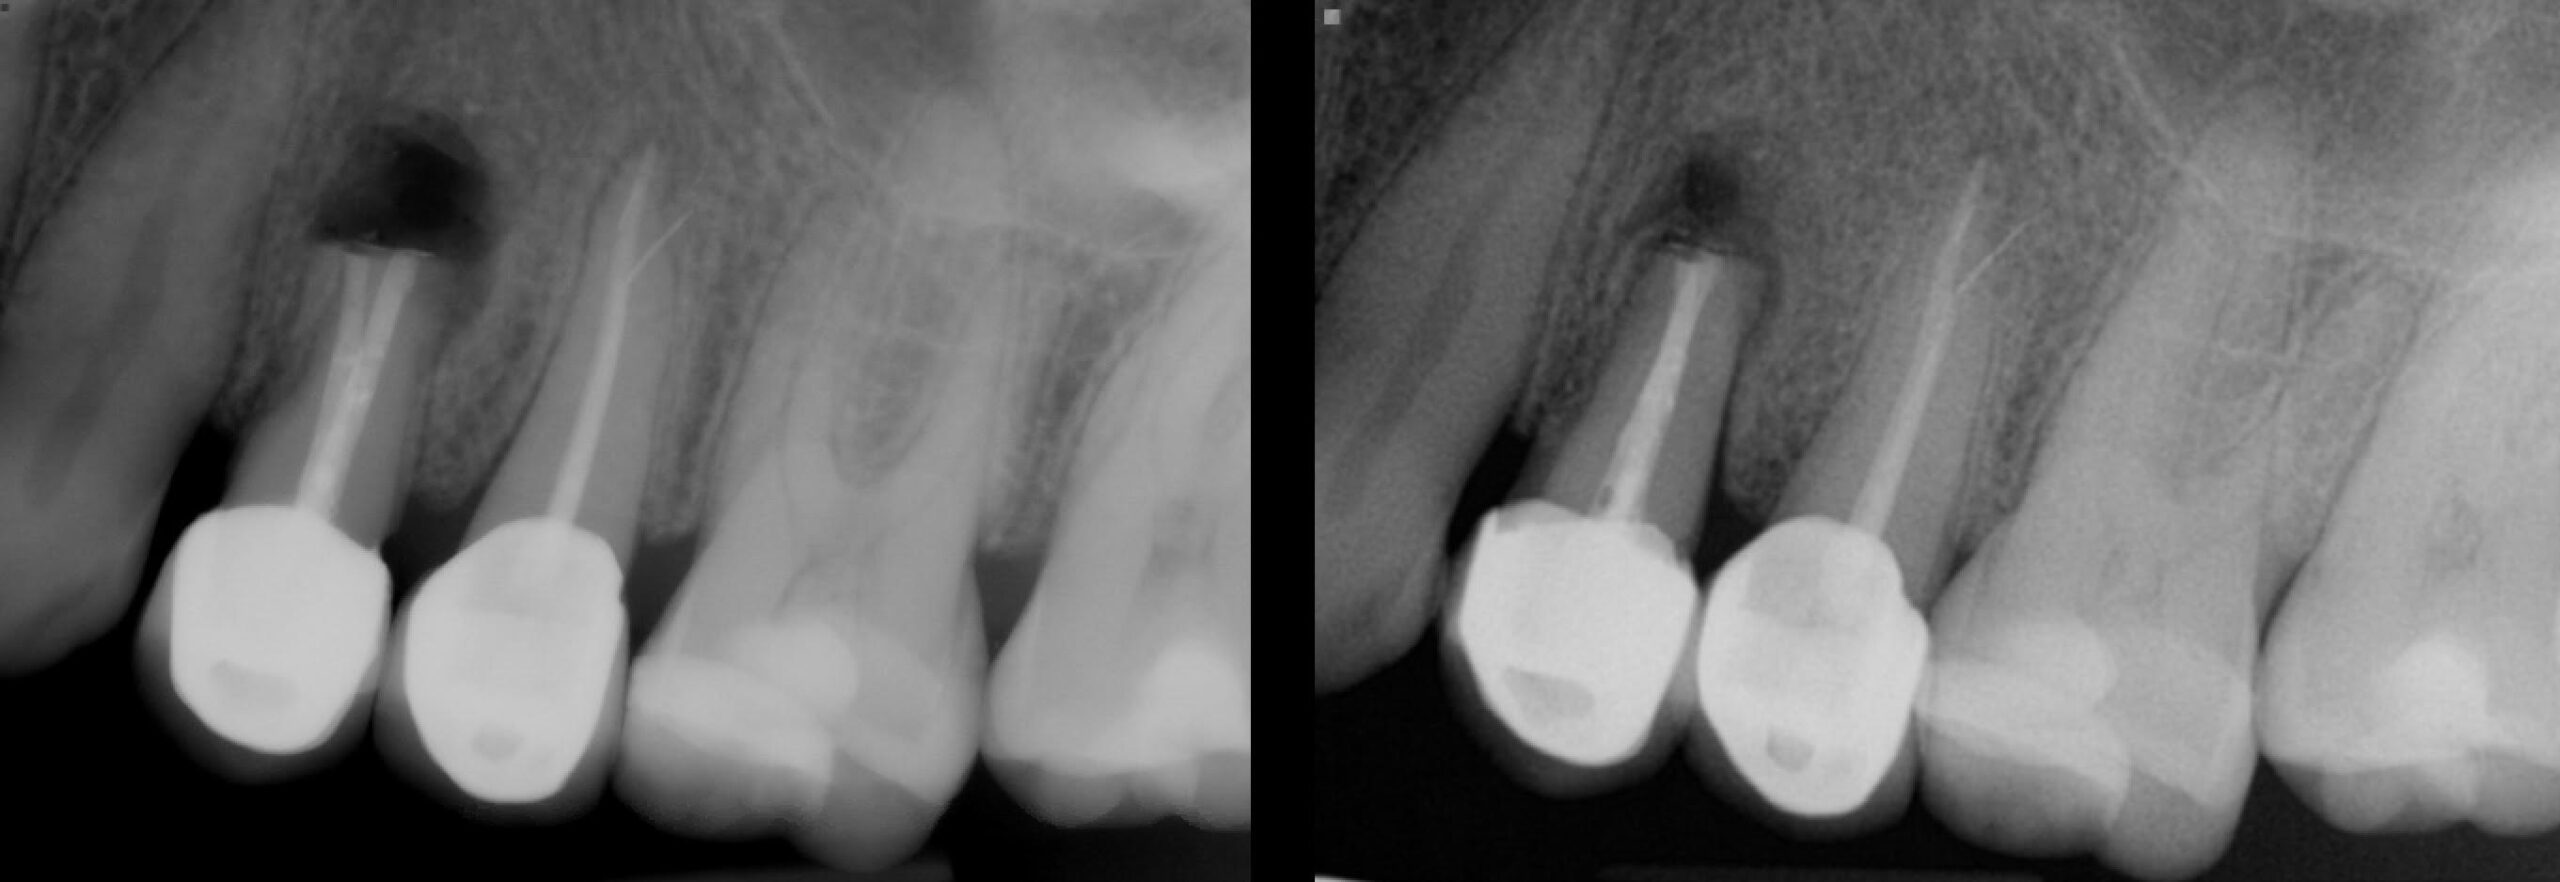

Actual “Before and After” X-rays

Patient’s tooth with previous endodontic treatment failing. Note the bone loss at the end of the roots which is indicative of a periapical infection.

The ends of the roots (apices) have been shortened, the bone has been manually cleaned and the ends of the roots have been filled or plugged with a biocompatible filling. This will help the bone regenerate.